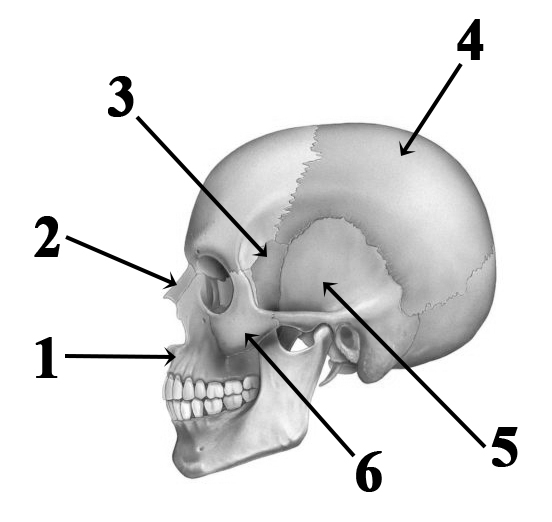

Анатомия: Блоки и сесамовидные кости в деталях